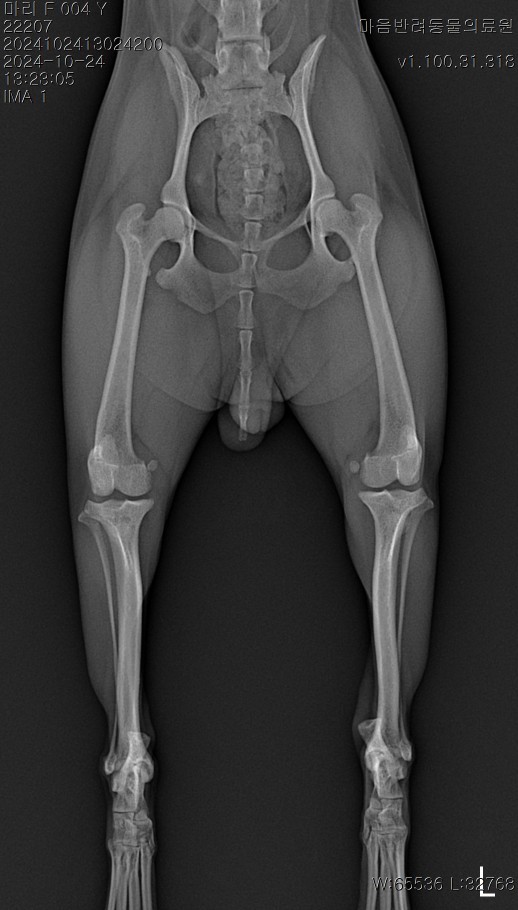

Thu 24.10.24 검진

My Day 2024.10.24 결기와 생일을 모두 환하게 밝혀준 꽃다발. 여전히 이쁘다는. 이번 꽃도 신기하게 오...